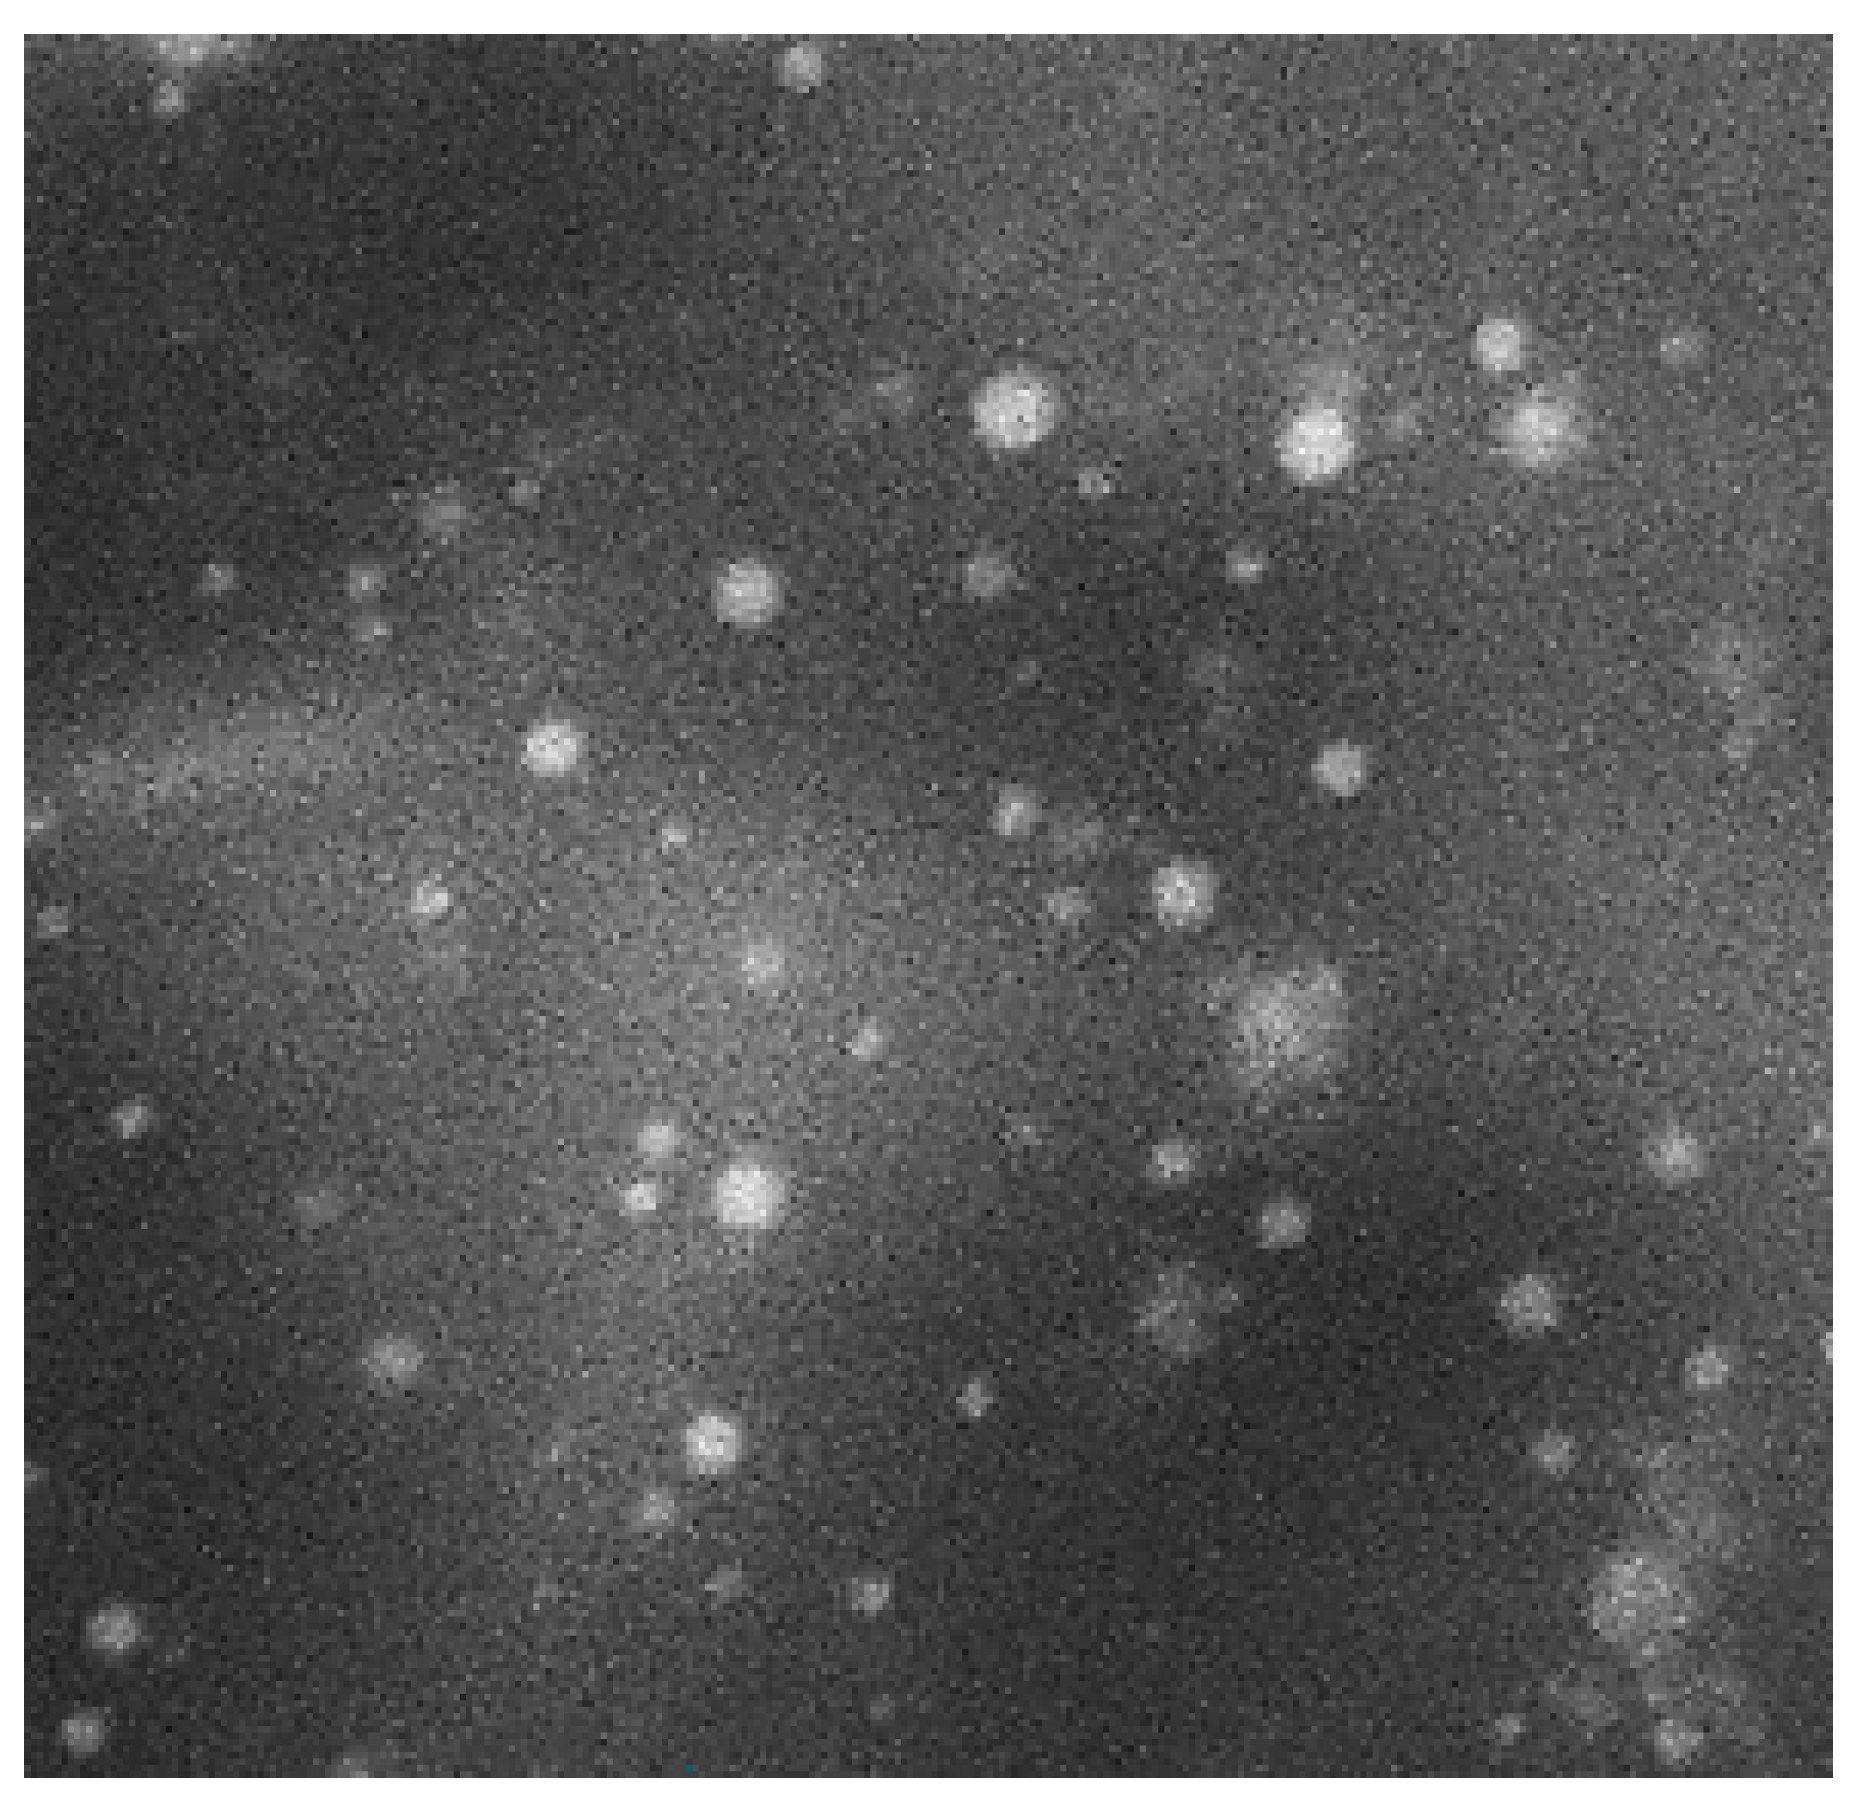

3.6.1. Morphological Characterization by SEM